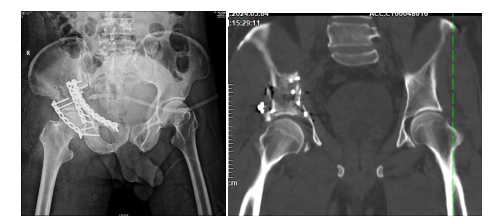

数字化与3D打印辅助模拟手术效果

为了攻克这一难题,云城人民医院骨科团队与华南理工大学解剖教研室、广州市第一人民医院数字骨科专家丁焕文采用MDT模式会诊,采用3D打印技术辅助手术。广州诺曼数字化医疗通过CT数据合成3D图像,精确复原了患者所有碎骨块的大小和位置。区人民医院团队在体外模拟了手术复位固定过程,作出精准术前规划,为手术的成功奠定了坚实基础。